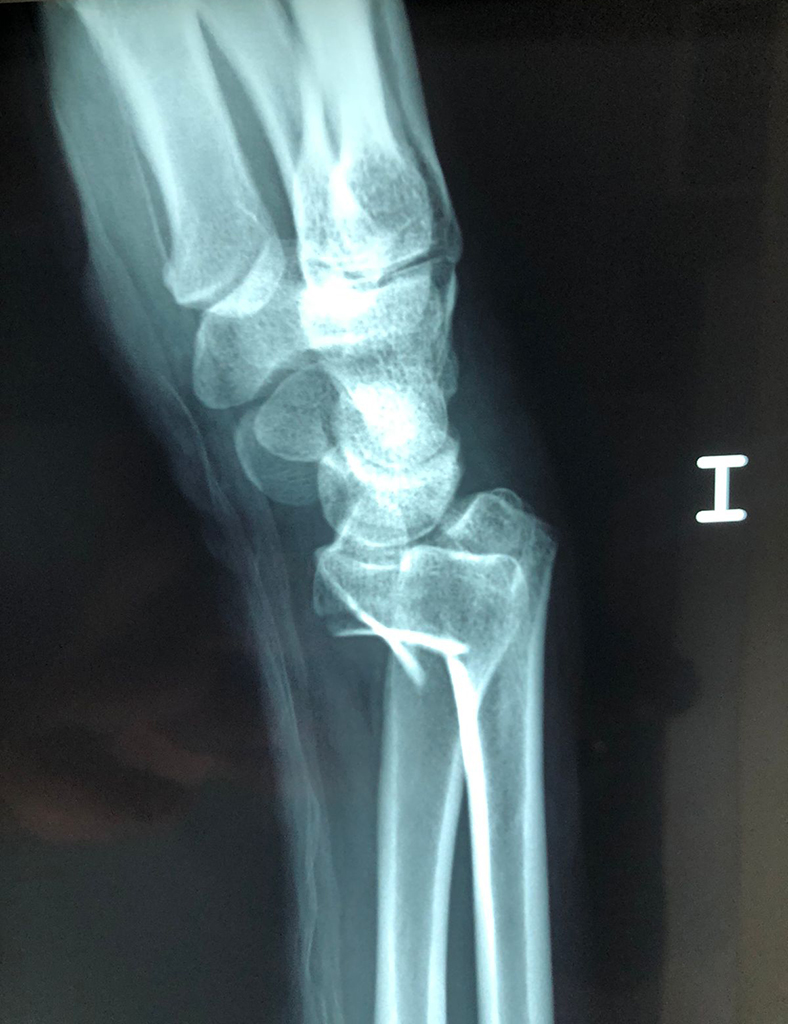

Cirugías de Calcaneo - Cirugías de Muñecas y Manos

Los procedimientos más comunes en cirugía de la mano son aquellos destinados a reparar traumatismos, incluyendo lesiones de tendones, nervios, vasos sanguíneos, y articulaciones; huesos fracturados; y quemaduras, cortes, y otros daños de la piel.